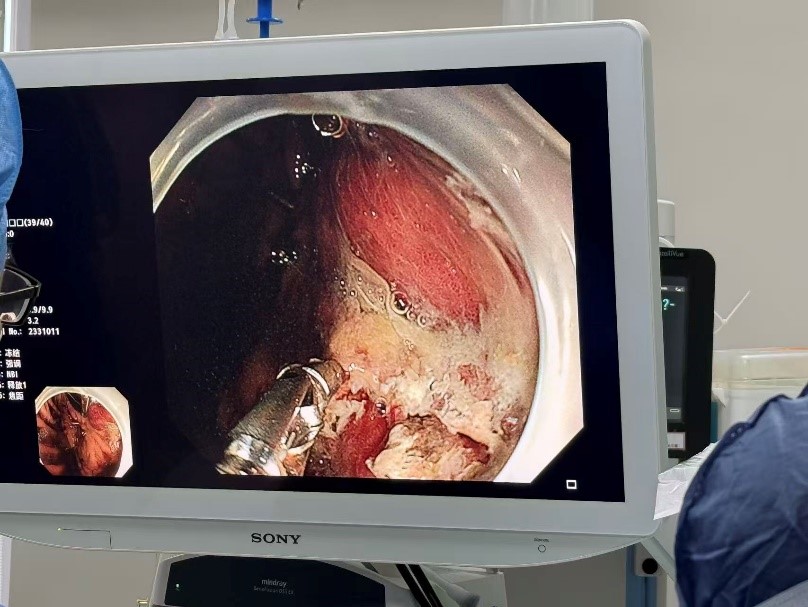

然而,考验接踵而至。韩阿姨突然出现致命的消化道大出血,口鼻和胃肠道不断涌出鲜血,血压难以维持。EICU迅速组织多学科会诊。消化内科医师团队立即施行急诊胃镜,发现了胃小弯侧存在的破口,危急时刻,普外科时林森副主任医师火速驰援,与家属沟通确认后,在ECMO支持下的极高风险中为患者进行胃穿孔修补术。术中清理血凝块达2000ml!术后第二天,患者血压再次持续下降,口鼻和胃肠减压管涌出了大量血液。耳鼻喉科医师在成功压迫患者口腔活动性出血点后,消化内科再次行急诊胃镜,并成功止血。随后,呼吸与危重症医学科曾大雄主任医师团队为患者进行纤支镜检查,吸取了堵塞韩阿姨呼吸道的大量脓痰。

急诊医学科、呼吸与危重症医学科、胸外科、血管外科与介入科、放射科、超声科等专家迅速集结共同商讨诊疗方案。研究讨论决定:呼吸方面,由超声科行超声下定位,胸外科医师置入胸腔引流管引流积液并送检,并邀请院内外多位呼吸科专家会诊。胃出血方面,再次由消化内科医师行胃镜止血。